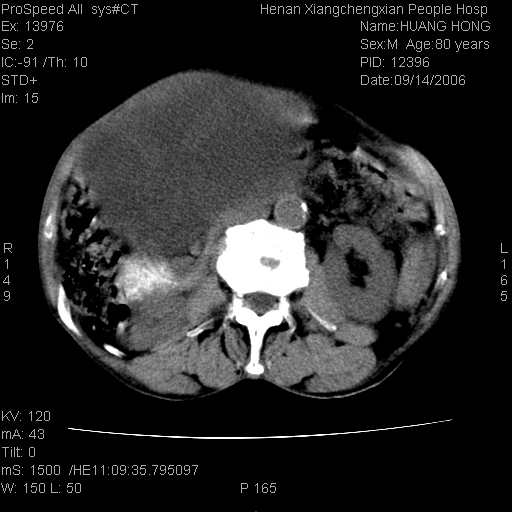

患者, 男, 80岁, 发现上腹部包块1年余,无其它不适.2006-9-14ct片是喝水后扫描2006-9-15ct片没喝水扫描![]() ![]() ![]() ![]() ![]() ![]() ![]() ![]() ![]() ![]() ![]() ![]() ![]() ![]() ![]() ![]() 以上是喝水片 以下是空腹片 ![]() ![]() ![]() ![]() ![]() ![]() ![]() ![]() ![]() ![]() ![]() ![]() ct:胰腺前方、肝脏与胃之间可见巨大类圆形囊性低密度影,大小约152mmx145mmx118mm,上缘平t11椎体上缘,下缘平l3椎体下缘,密度均匀,ct值15hu,其内呈多房分隔,囊壁薄且光滑,边界清晰,周围组织及器官明显受压。肝脏实质内未见异常密度影,胆囊未见异常,胰腺密度未见异常,脾脏大小、形态及密度未见异常,腹膜后间隙未见肿大淋巴结影。 印象:胰腺前方、肝脏与胃之间巨大类圆形囊性低密度影.性质待定。多考虑:.肠系膜巨大囊肿。 守望可可西里发言:支持楼主,考虑肠系膜囊肿,多为小肠系膜。 ysxyy发言:我总觉得这个病人虽然很像肠系膜囊肿,但还是应该强化一下; 下面这几幅图里肿块和主动脉的关系不太清,不知能否除外血管性来源? ![]() ![]() ![]() 病理结果:横结肠系膜间叶瘤.部分区域间质细胞增生活跃. 病理图片 ![]() 良性间叶瘤:是指由两种或两种以上的间叶组织所构成的混合性肿瘤.肿瘤仅发生在腹膜后和肠系膜,.前者较后者多发.良性间叶瘤常发生在肾或四肢,腹膜后较少见,各年龄均可发病.女多与男,预后较好,但术后易复法. 恶性间叶瘤:由两种以上恶性间叶组织成分组成. 光镜:肿瘤由脂肪/血管/平滑肌构成. 原贴地址: http://www.radinet.com.cn/forum_view.asp?forum_id=4&view_id=16217 ok |